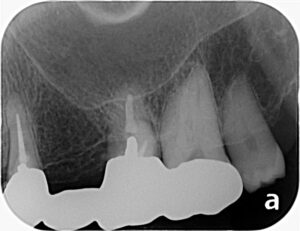

今回は左上の症例です。上のレントゲンに写っている左の歯が、一見何もなさそうに見えますが、根が破折していて抜歯になりました。